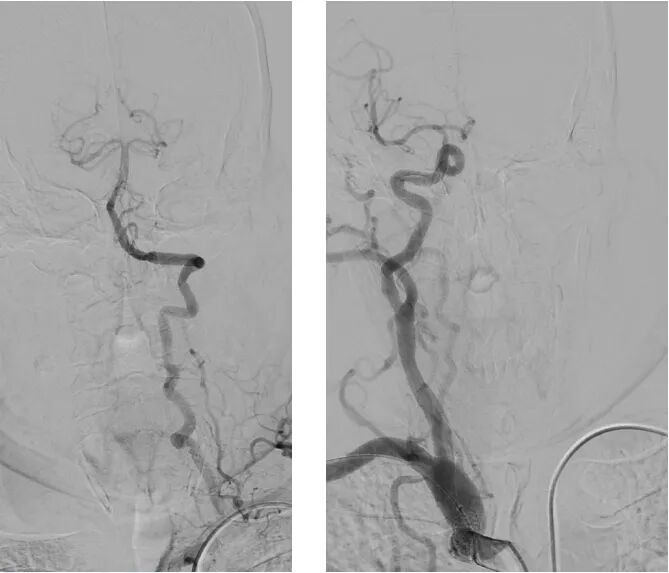

·右侧桡动脉入路造影

明确左侧锁骨下动脉起始部重度狭窄;

同时发现起始部斑块为溃疡斑块。

·球扩后植入9-30自膨颈动脉支架

桡动脉鞘怎么读【REPLAY·周三全桡日】王鹏:双侧桡动脉入路 锁骨下支架_https://www.jmylbn.com_新闻资讯_第19张